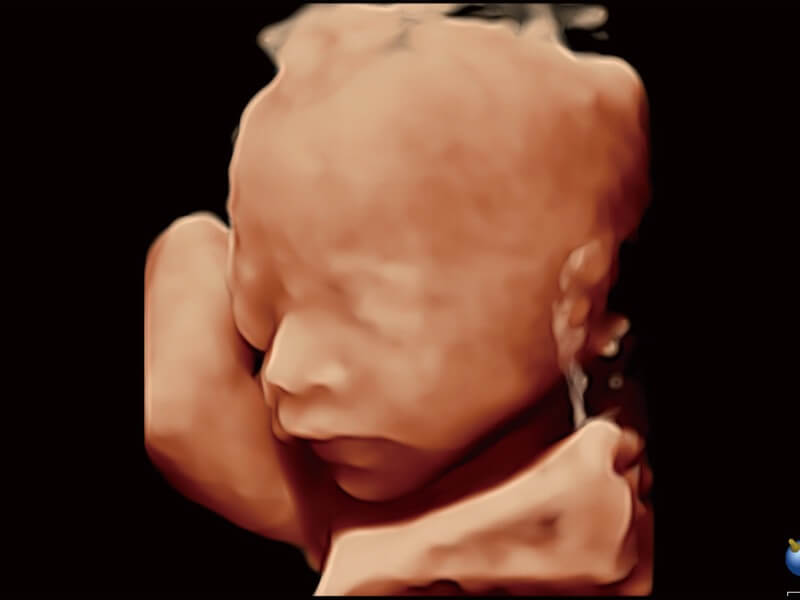

Die Visualisierung des 3D-Gesichts des Fetus ist wichtig für die Diagnose von Gesichtsanomalien. Durch Auto Face können Hindernisse und Artefakte wie Nabelschnur, Plazenta, Gebärmutter und Extremitäten einfach entfernt werden, um eine optimale Ansicht des fetalen Gesichts zu erhalten.